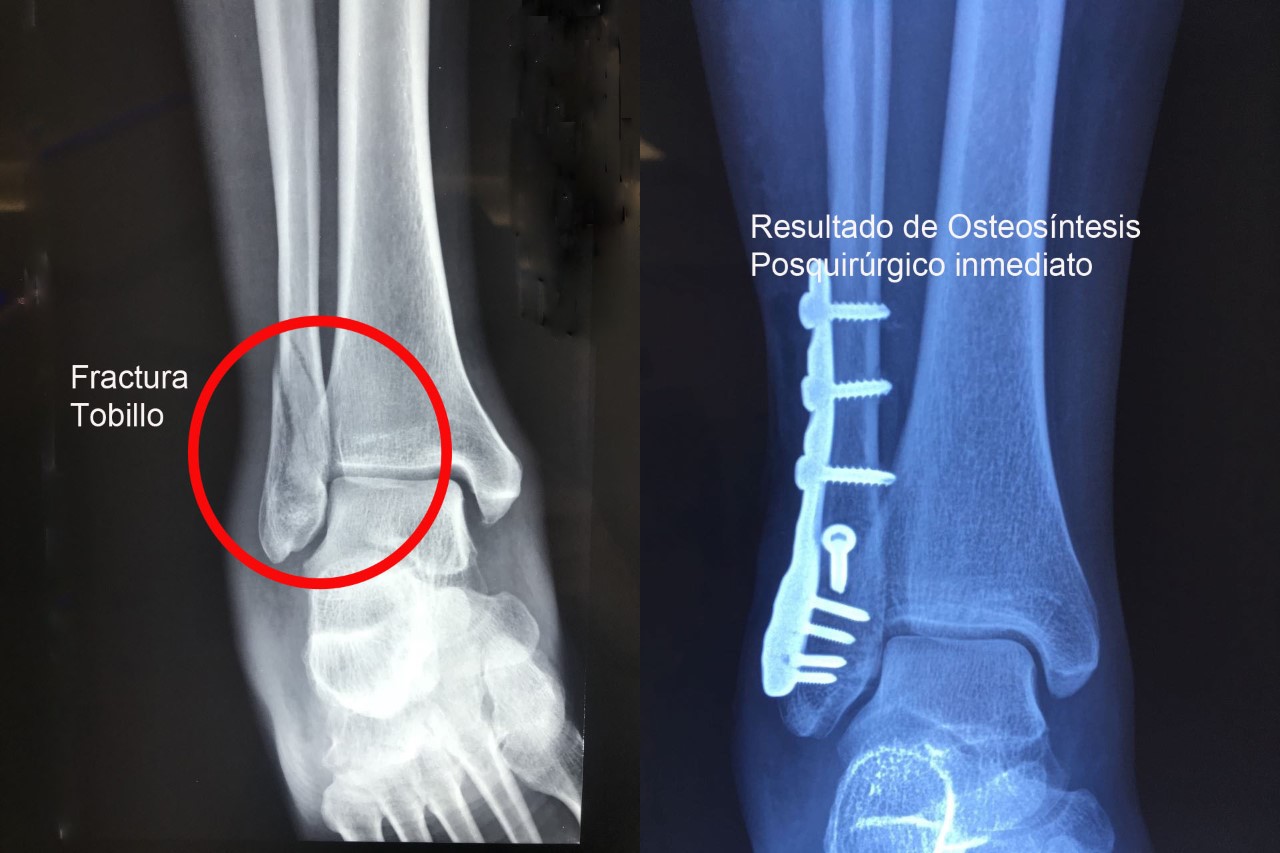

Una fractura ósea es la ruptura de un hueso, la cual puede presentarse por diversas causas y su tratamiento dependerá de la magnitud, sitio anatómico y de las enfermedades concomitantes. Algunas pueden manejarse de forma conservadora con solo inmovilización y hay otras que requieren de un tratamiento quirúrgico. A continuación, podrá ver algunos casos quirúrgicos, dando clic a la zona del cuerpo afectada.